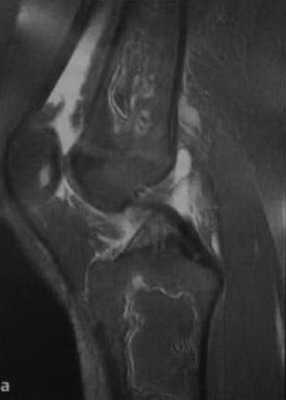

а, b Инфаркт зрелого костного мозга. (а) Сагиттальная протонная плотно-взвешенная МРТ с подавлением МР-сигнала от жировой ткани. Изображение демонстрирует гирляндовидный склеротический край и центральный участок с сигналом жирового костного мозга. Множественные некротические зоны расположены преимущественно в метадиафизальной области, однако несколько находятся непосредственно рядом с суставом, в связи с чем имеется риск уплощения суставных поверхностей;